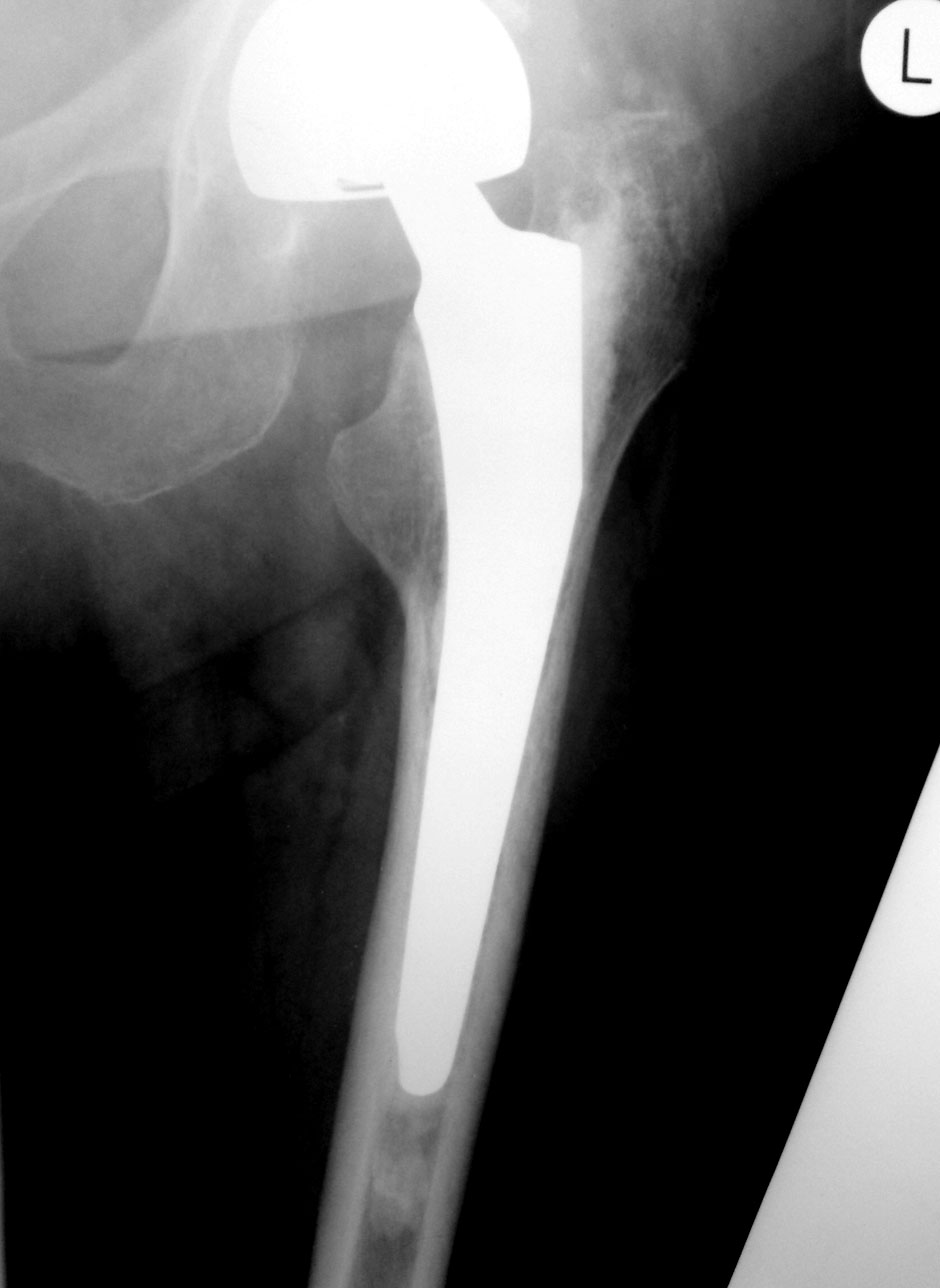

Как оценят коллеги состояние этого сустава? Возраст 77 лет, пол женский. Операция 8 мес назад.

Ножка протеза беспокойства не вызывает.

По положению компонентов претензий нет. Смущает приведение в т/б суставе, но скорее всего лаборант ногу не отвел, а вообще приводяще-сгибательная контрактура у пожилых пациентов обычное дело.

Не совсем правы Вы, Анатолий Владимирович... Ссылка о тотальном протезировании, а в приведенном случае - нетотальное, частичное замещение, головка бедра и шейка замещены протезом. Так что выводы о бедренной ножке протеза по этой ссылке сделать можно, и только.